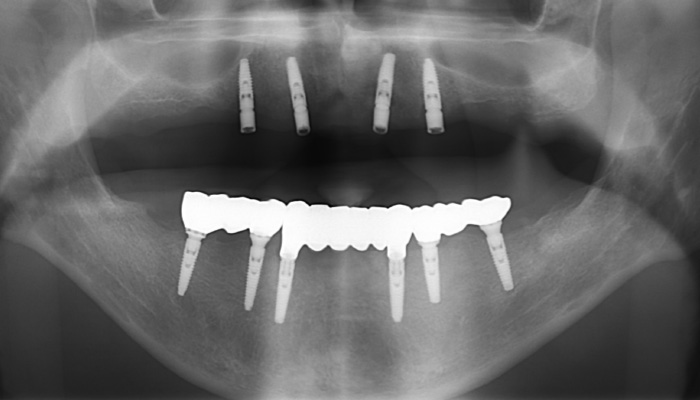

インプラント症例

年齢・性別 | 50代・男性 |

---|---|

主訴 | インプラント治療希望 |

治療内容 | 上顎は4本のインプラントを用いて、 インプラントオーバーデンチャー 下顎は6本のインプラントを用いて、 3ユニットのインプラントブリッジ |

費用 | インプラント 1本¥440,000〜¥462,000 |

期間 | 約1年 |

副作用・リスク | インプラント埋入手術後に 腫れる場合があります。 |

担当者所見 | 欠損部位を長期間、放置していたため、咬合崩壊を呈していた。

食事が困難になってきたため、インプラント治療を希望。 上顎は4本のインプラントを用いて、インプラントオーバーデンチャー。 下顎は6本のインプラントを用いて、3ユニットのインプラントブリッジ。 |